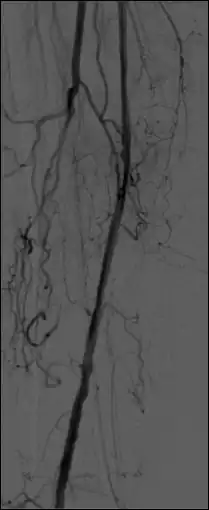

Open an image sequence in the 2D Viewer, and open the same sequence for a second time, so that the image sequence is displayed in two separate windows. Turn off synchronization by selecting 2D Viewer | Stack Syncronize | Off. Drag the icon of one window and drop it onto the image in the second window to call up the fusion functions and click the Subtraction button:

Pixel values displayed for subtracted images refer (correctly) to subtracted images with this option, although pixel shifting is not available. The Thick Slab module can be used to (effectively) integrate both mask images (before subtraction) and live images (before and following subtraction) so as to improve image SNR and to generate a vascular trace.